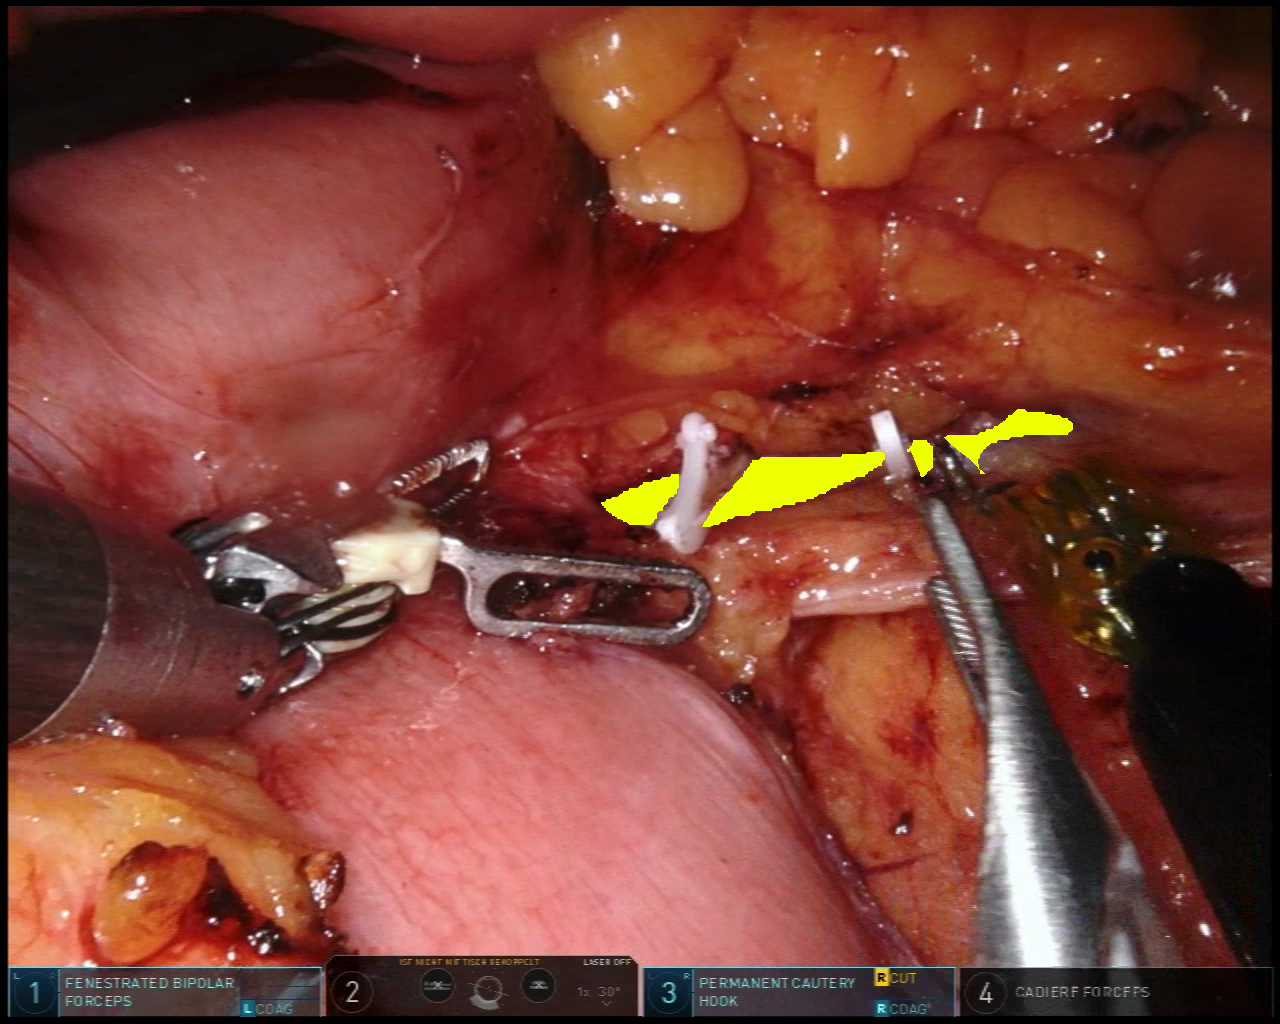

While the application of our proposed methodological approach to spectral imaging data represents our main focus, we also demonstrate the capability of our method in a non-spectral imaging dataset. More specifically, we make use of an RGB laparoscopic dataset that shares many similarities in terms of anatomical content and annotation style.

The Dresden Surgical Anatomy Dataset (DSAD[10] comprises 13195131951319513195 laparoscopic images from 32323232 patients of robot-assisted anterior rectal resections or rectal extirpation surgeries. Images provided in the dataset were extracted from the video and were stored in PNG format at a resolution of 1920×1080192010801920\times 10801920 × 1080. The annotation of 11111111 abdominal organs provided pixel-wise segmentation with multiple inclusion criteria for anatomical structures, resulting in sparsely annotated images across the dataset. The majority of annotations in this dataset only account for a single organ per image. However, a subset of the data is associated with multi-organ segmentation for all 11111111 anatomical structures. This includes a total of 1430143014301430 images in 32323232 patients.